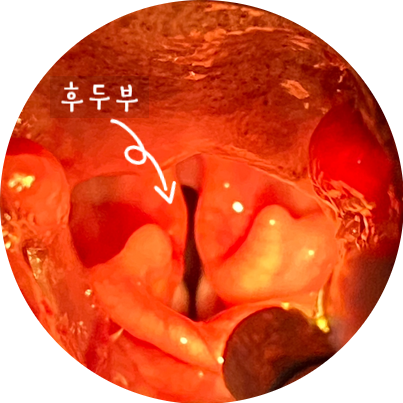

내시경 검사로 후두부를 확인했어요. 눈으로 확인하기 어려운 작은 변화도 내시경 검사를 통해 자세히 조사할 수 있었습니다.

◆ 후두부 확인

후두부를 검사할 때는 연골의 크기 차이밖에 문제가 되지 않았습니다. 그래서 후두부에서 구강을 향해 천천히 내시경을 채취하면서 검사를 해 보았습니다.